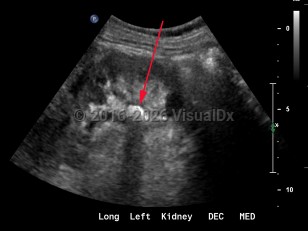

Hydronephrosis

Renal calculus

Renal nutcracker syndrome

Ureteral calculus